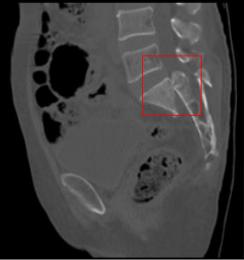

正常人CT

2017年7月3日,患者经多方打听,转至我院骨伤一科进行诊治。患者入院完善相关检查,其中骨盆CT显示:骶1骨折(粉碎性骨折),继发相应椎管重度狭窄。再结合患者病史症状体征及其他影像学资料,最后诊断为:不稳定型骶骨骨折。